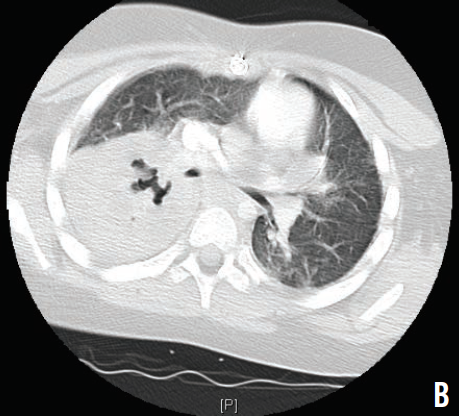

Because of his worsening leukocytosis and respiratory status, he was transferred to the intensive care unit. An infectious disease specialist was consulted, and laboratory studies for various viruses and bacteria were ordered. Vancomycin and meropenem were started. Due to progressive respiratory distress and eventual respiratory failure, the patient was intubated. A computed tomography scan of the chest showed necrotizing right lung pneumonia with diffuse pneumonitis (B). Urine cultures were positive Legionella pneumophila, and he was started on intravenous azithromycin.